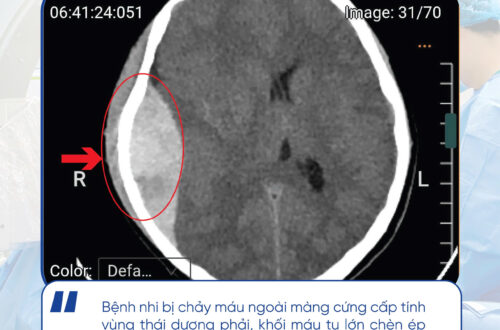

🚨 NGÃ XE ĐẠP, BÉ TRAI 11 TUỔI CHẤN THƯƠNG SỌ NÃO NGUY KỊCH, ĐƯỢC PHẪU THUẬT CẤP CỨU KỊP THỜI

Mới đây, Bệnh viện Hữu nghị Lạc Việt tiếp nhận một trường hợp chấn thương sọ não nguy hiểm ở bệnh nhi Đoàn Nguyên Tú (sinh năm 2014, xã Sơn Thủy, tỉnh Tuyên Quang). Theo người nhà, khoảng chiều tối,...